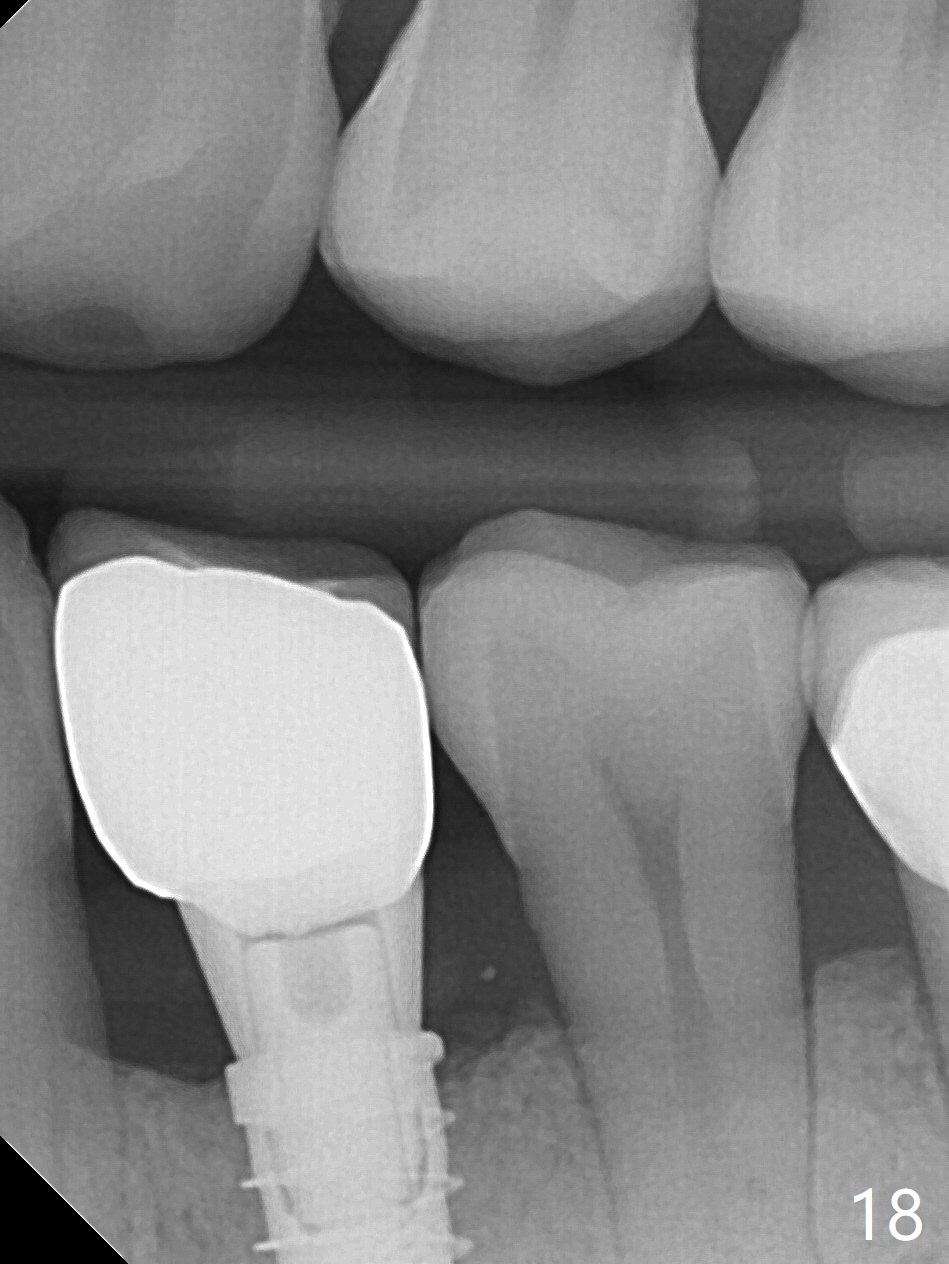

The implant seems to have osteointegrated 4 months postop (Fig.9).  When a permanent crown is fabricated, it should have normal occlusal and buccal contour (from Fig.11 (provisional) to 12 red and black curved lines) as well as the buccal cervical extension (Fig.12 to cover the buccal gingiva (Fig.10 *).  If the lingual margin of the abutment is too prominent, return the case and the abutment will be changed to the one with 2 mm cuff (existing 3 mm).  The lingual margin of the abutment will be trimmed.  The patient is not pleased with the short buccal margin of the crown after cementation (Fig.13).  In fact the provisional should have been fabricated so that the its buccal margin should be subgingival and within the gingival outline.  It may prevent buccal plate collapse.  In fact the crown dislodges 1 year post cementation.  The lingual margin is prep lower to increase the abutment height.  Impression is taken.  Although the access hole is unnecessary for cementation, it acts as an escape hole so that there is no excess cement cervically (Fig.14-18).